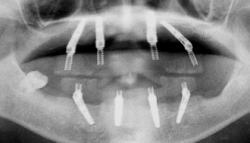

| 上顎はいつ抜けてもおかしくない状態であったため、直ちにAll-on-4を施術しました。 下顎も重度の歯周病で状態は良くありませんでしたが、患者様の希望もあり、抜歯せず、現在経過観察中です。 |